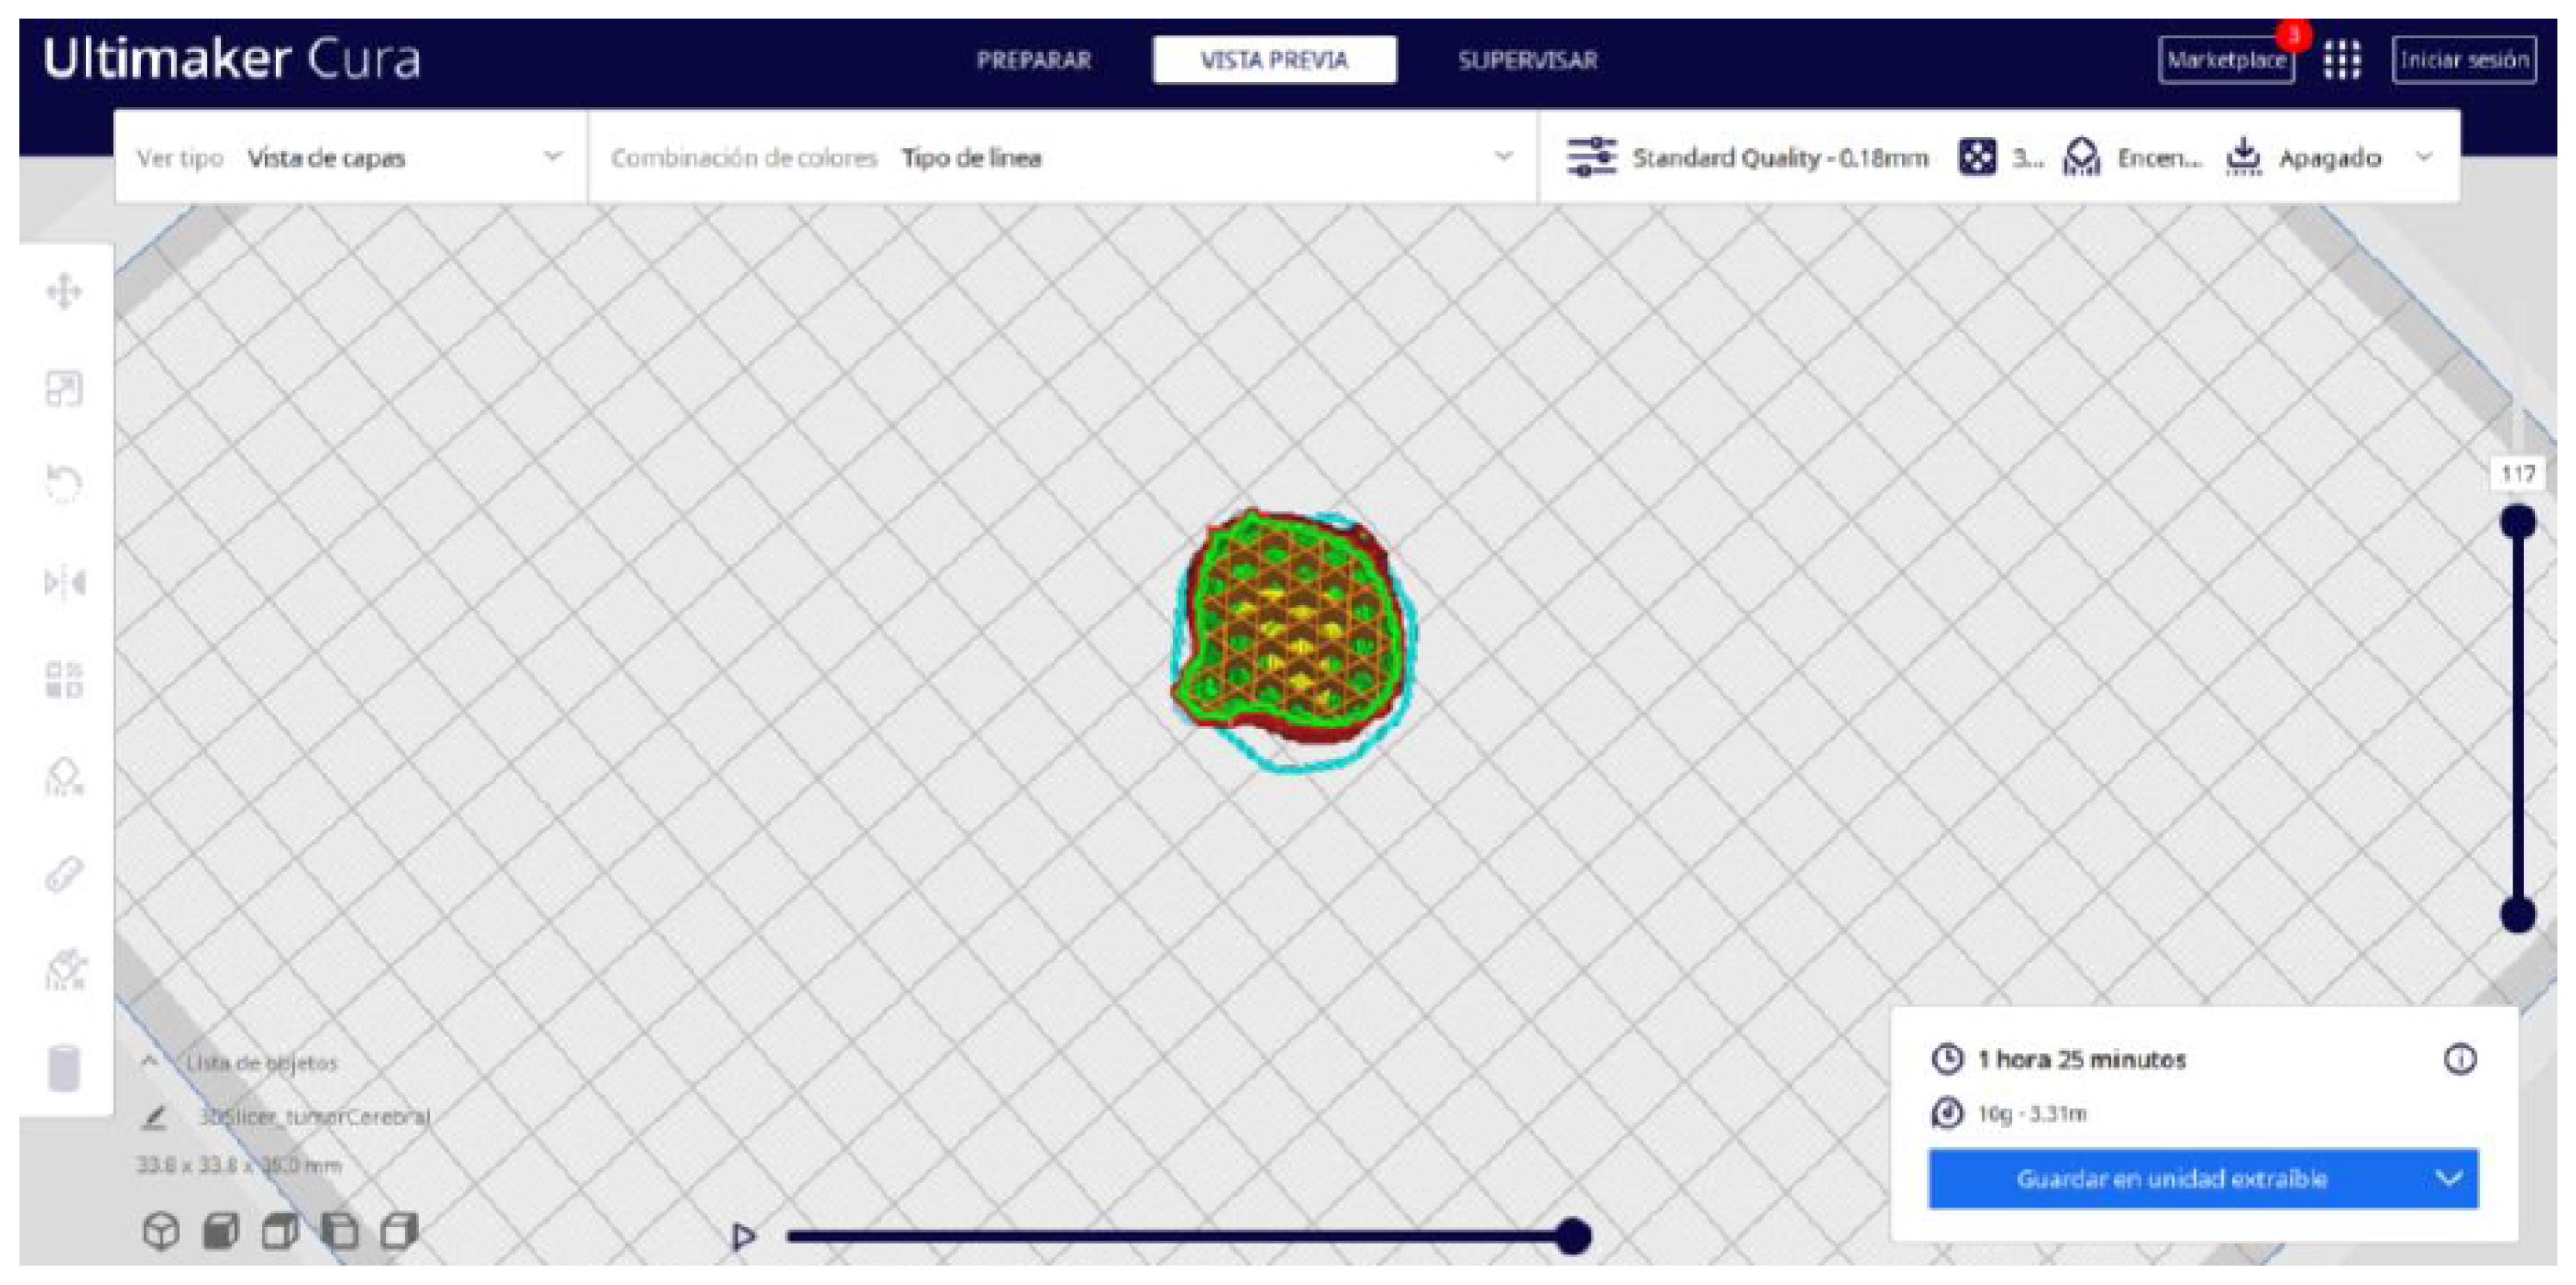

3.3.2. STL-to-GCODE Files

- In order to continue the STL file to GCODE conversion process, select the “Segmentation” option in Ultimaker Cura.

- The segmentation tool provides valuable information such as the estimated model weight and estimated printing time, among other crucial data.

- Once the segmentation is complete, go to the “Preview” option. Here, a sidebar will appear on the right side of the screen, giving you the ability to preview the materialisation process layer by layer, from the base to the top of the model.